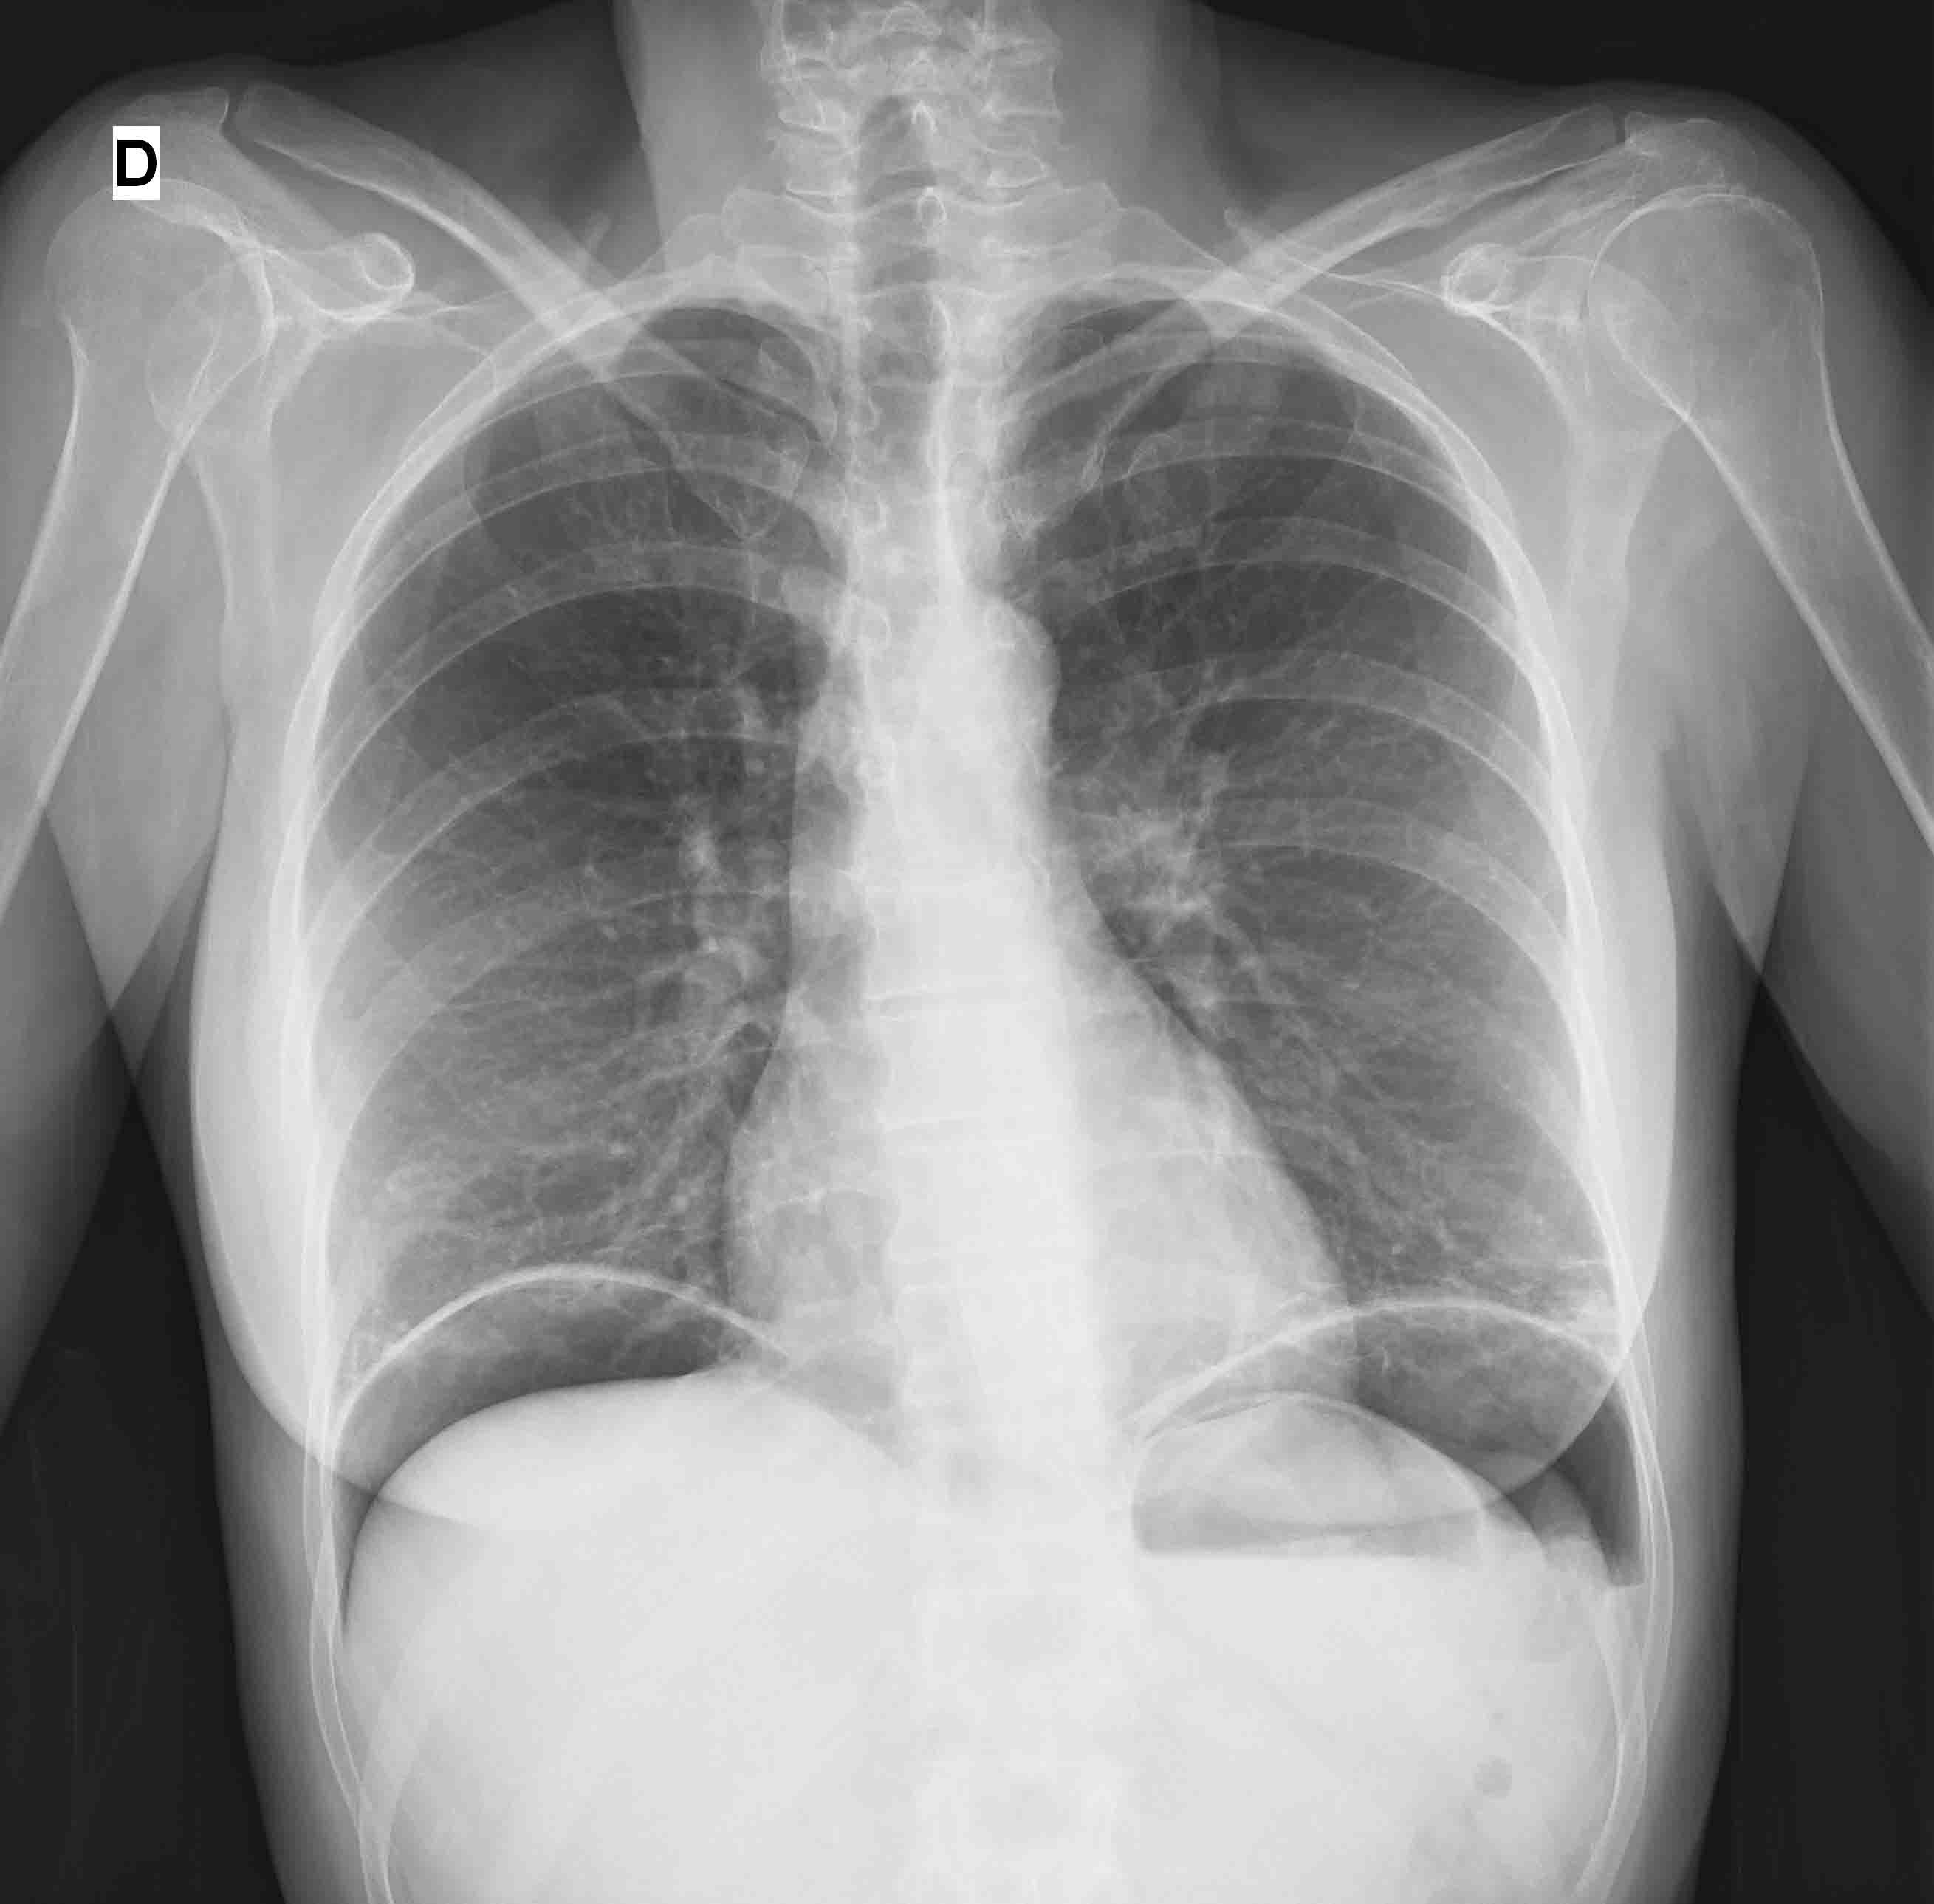

• No pase por alto las pistas extraabdominales. En pacientes cuyo examen abdominal no es revelador, ampliar el alcance del examen físico, ya que la enfermedad extraabdominal puede presentarse como dolor abdominal (por ejemplo, infarto de miocardio, neumonía, embolia pulmonar, patología renal u otra patología retroperitoneal)